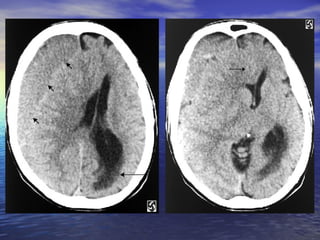

• #9 Slide #8 Epidural Hematoma Case A 32 y/o man presented to the ER after slipping on ice in his driveway. The patient fell backwards and hit his head on the ground. The patient got up and returned to his house and told his wife what had happened. After about 20 minutes of sitting the patient began complaining of a headache. Approximately one hour after the fall the patient became disoriented and obtunded. The patient's wife immediately called an ambulance, which brought him in to the ER. On arrival the patient was obtunded to the point that he could not answer or respond to questions. The CT on the left was taken shortly after arrival. Diagnosis: Epidural Hematoma On CT, epidural hematomas appear as well-defined, high attenuation lenticular or biconvex extra-axial collections. Associated mass effect with sulcal effacement and midline shift is frequently present. Overlying linear skull fractures can often be visualized on bone windows. If an epidural hematoma appears heterogeneous, containing irregular areas of lower attenuation, this can indicate active extravasation of fresh unclotted blood, requiring immediate surgical attention. Alternatively, areas of low attenuation can represent serum extruded from the clot.

• #10 Slide #9 CT of the head obtained without intravenous contrast enhancement shows a biconvex high-attenuation epidural hematoma adjacent to the right frontal lobe ( arrows ). The lesion extends superiorly to the level of the body of the lateral ventricle ( arrow )

• #11 Slide #10 and inferiorly to the roof of the right orbit (arrow). Mild mass effect is exerted on the subjacent brain parenchyma. A fracture is visible extending through the right side of frontal bone (arrow)

• #12 Slide #11 to the roof of the right orbit (arrow) with associated extracranial soft tissue swelling (arrow).